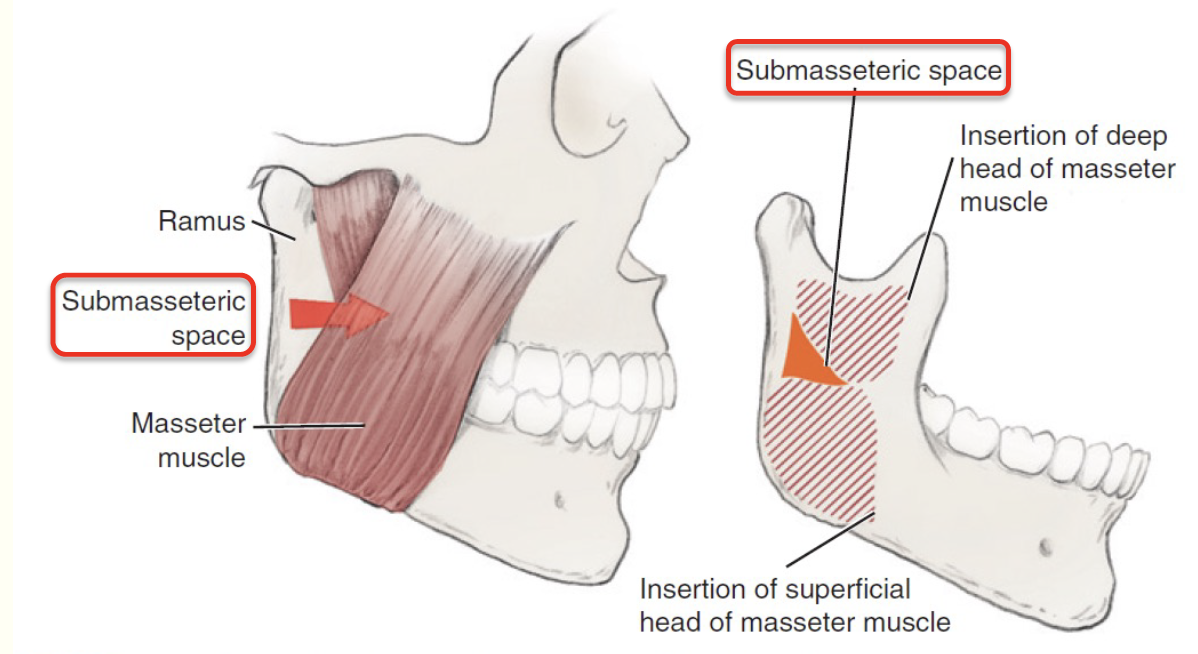

Submassetric space